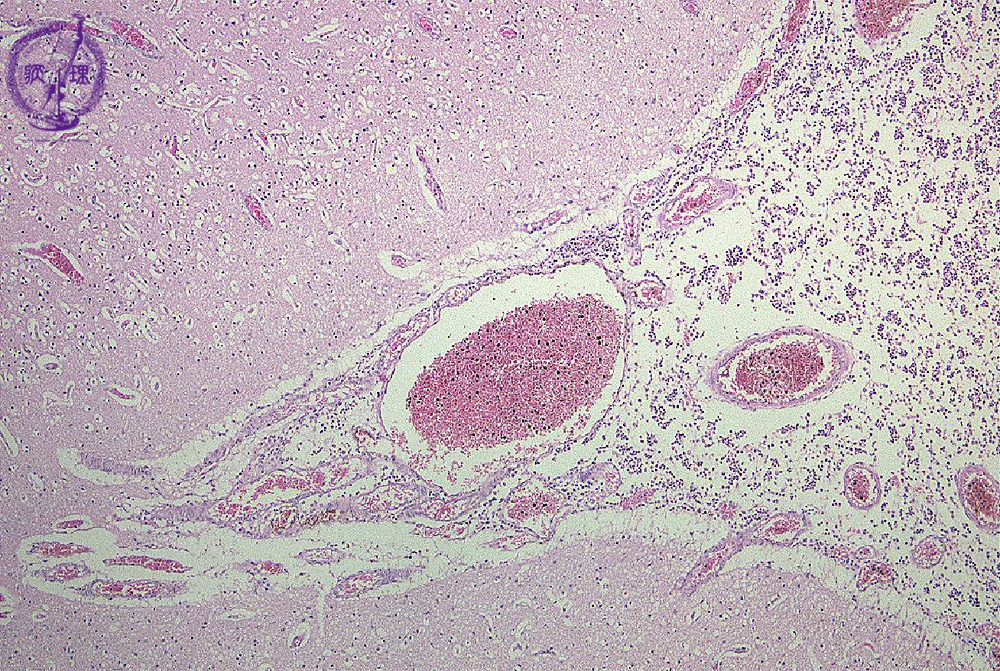

Microscopic findings (H.E. low magnification): Extensive infiltration of inflammatory cells detected in the subarachnoidal spaces but not in the cortex.